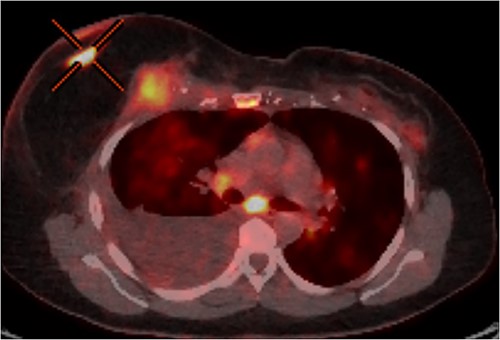

In June 2020, RC noted changes to the skin of her right breast. These changes were associated with a palpable mass deep to her nipple areolar complex. Biopsy of this lesion found it to be recurrent invasive ductal carcinoma, which was hormone receptor negative and HER2 receptor positive. MRI and PET imaging traced the lesion from the skin flap, via the TRAM flap pedicle, into the thoracic cage to involve the pleura (Fig. 1). Regional metastases to the right axillary lymph nodes and distant metastases to the mediastinal nodes, lungs bilaterally and spine were evident.

PET-CT axial slice showing both superficial and deep components of the local recurrence with associated malignant pleural effusion from direct extension to the pleural cavity.